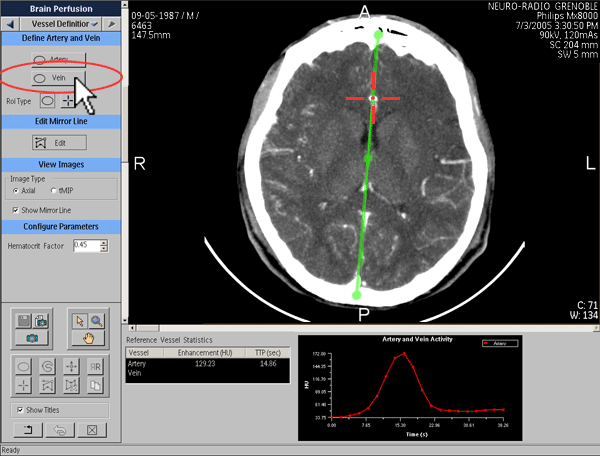

Définition de la fonction de sortie veineuse